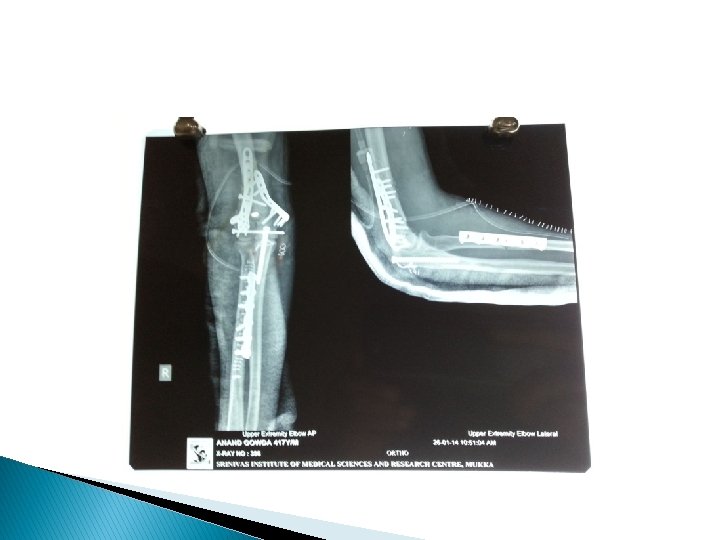

I TYPES 1. Simple 2. Compound II 1. Complete Displaced -Shift, Tilt, Rotation Un Displaced 2. Incomplete III 1. Linear Transverse Oblique Spiral - Butter Fly 2. Comminuted 3. Segmental 4. Bone Loss <50% >50%

A. O. Classification: � Ø Each long bone is numbered. First digit Bone Ø Second digit Ø Third letter AO/ASIF Segment 1– 4 Type A – C Proximal & distal A - C

Comminuated fracture � Two or more bone pieces - high energy trauma